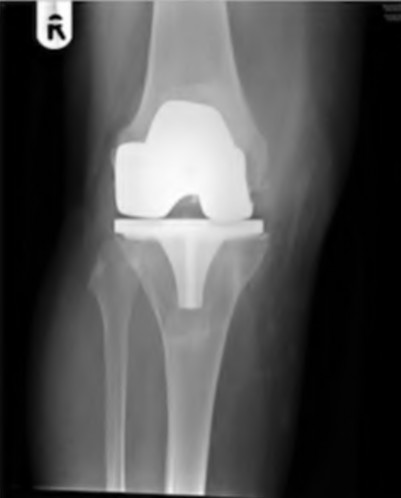

A 64-year-old woman with osteoarthritis underwent bilateral total knee replacement 3 years ago. Current radiographs are shown in Figure A. She reports a 3-month history of bilateral knee pain while at rest and increasing swelling in the knees. Her ESR and CRP are elevated and bilateral knee aspiration cultures reveal Staphylococcus aureus. What is the most likely outcome if the patient undergoes simultaneous, bilateral knee resection arthroplasty with cement spacer and a course of intravenous antibiotics?

This patient presents with bilateral total knee arthroplasty infection.

Wolff et al report Level 4 evidence of 18 patients followed an average of 5 years after bilateral TKA infection. Eleven patients were initially treated with attempts to salvage the original prosthesis (polyethylene l liner exchange, I&D, IV antibiotics and chronic oral suppressive antibiotics. With prosthesis retention, 9/11 (81%) developed recurrent infection at a mean of 15 months. The other 10 patients initially underwent resection arthroplasty with cement spacer and a course of IV antibiotics. Seven of the 10 (70%) underwent reimplantation at a mean of 3 months (6 weeks to 5 months) and none of the patients required revision at mean of two years follow up. Satisfaction rates were significantly higher among this group of patients. The authors advocate the protocol of bilateral TKA resection arthroplasty with cement antibiotic spacer and course of IV antibiotics followed by prosthesis reimplantation.